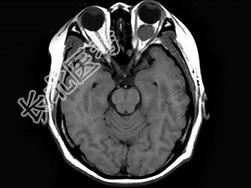

- 单项选择题女,47岁, 左眼球突出伴视力下降半年,MRI平扫及增强扫描见眶内占位性病变, 最可能的诊断是 ( )